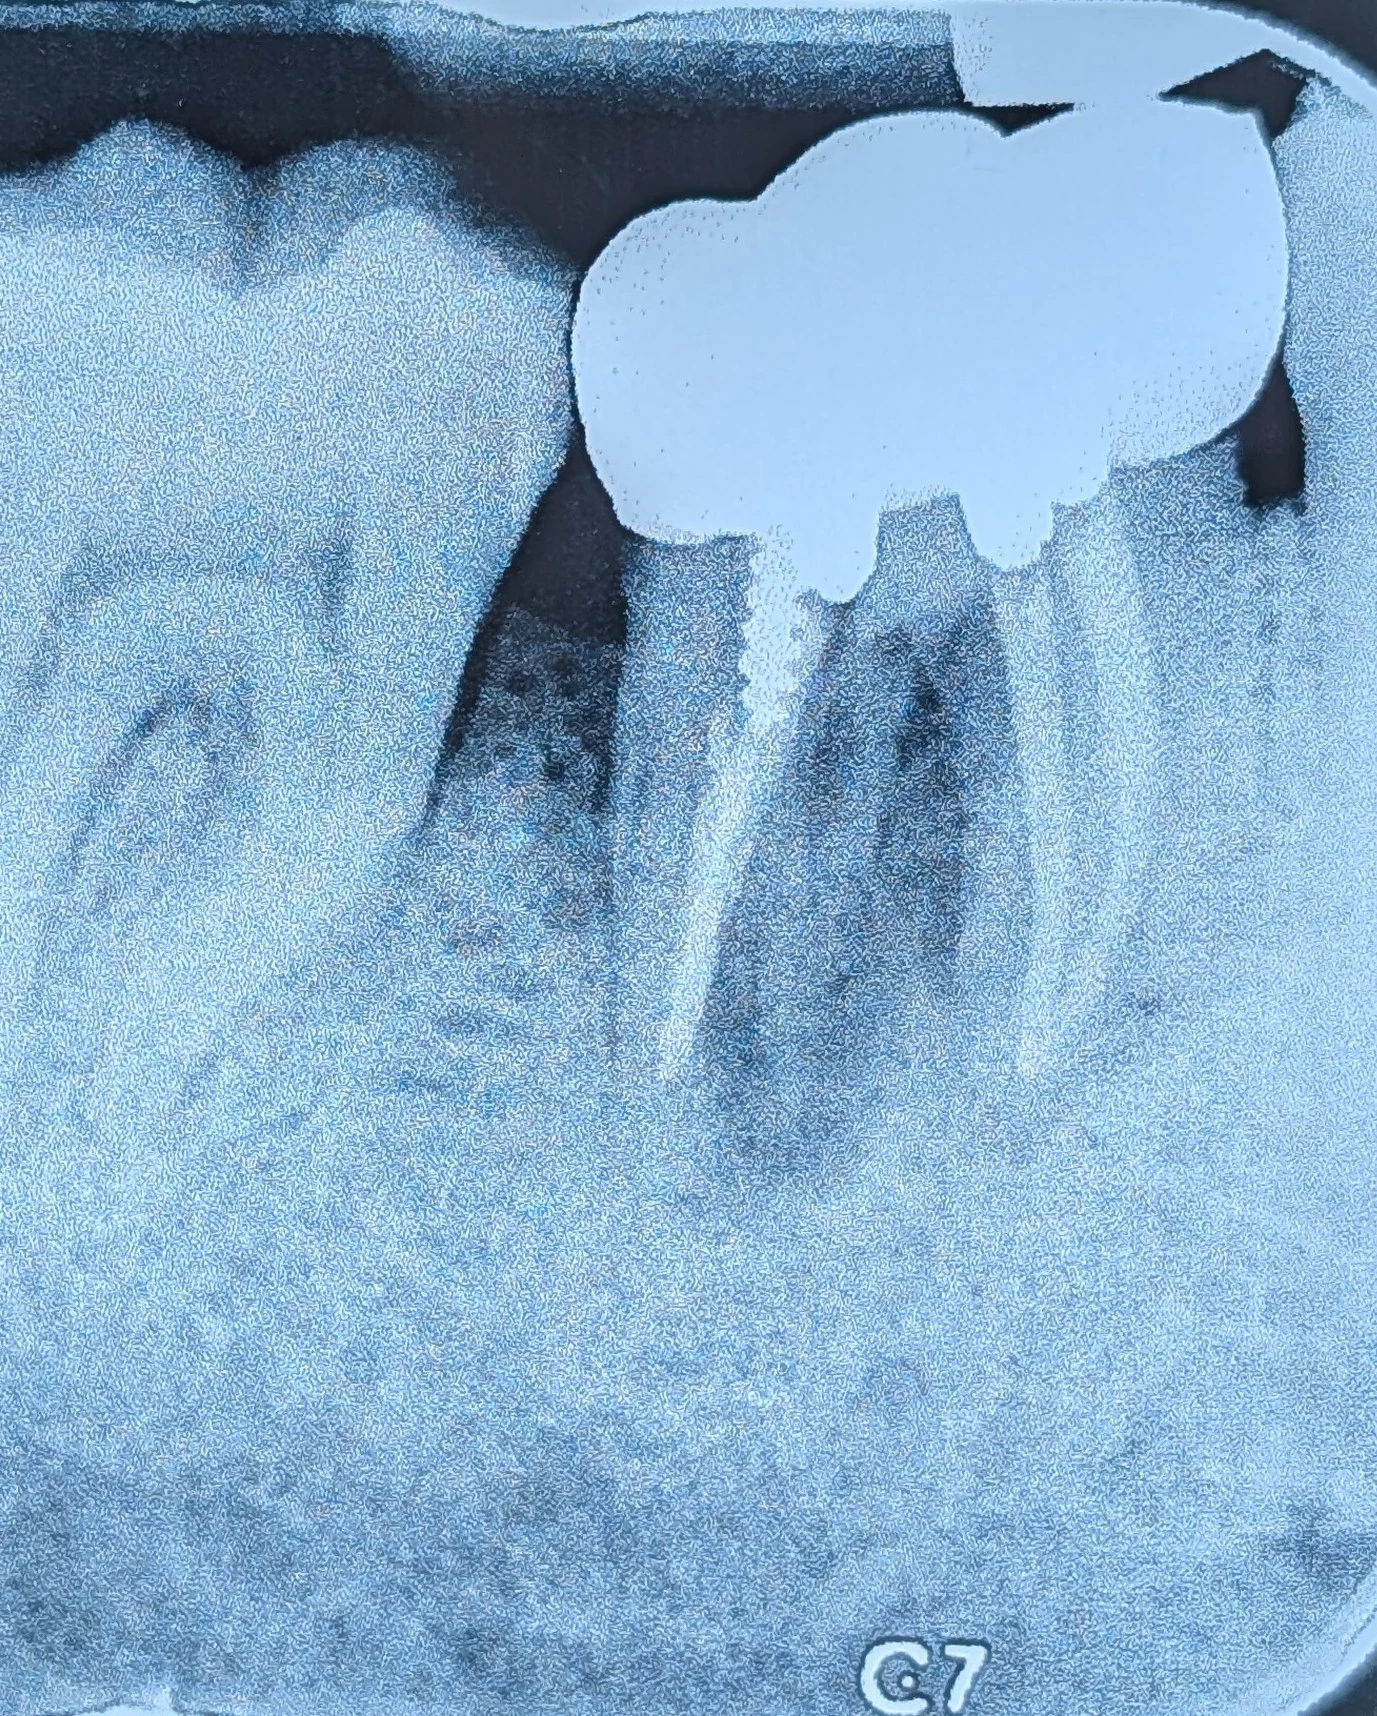

در این کیس، دندان حدود دو سال قبل روکش شده بود. در زمان درمان، کیفیت درمان ریشه به‌طور کامل قابل ارزیابی نبود و انجام آن توسط درمانگری با سابقهٔ نامشخص صورت گرفته بود.درمانگر ریشه نامه ی تایید داده بود.

امروز بیمار با درد و علائم عفونی مراجعه کرد و در بررسی تخصصی مشخص شد یکی از کانال‌ها در درمان اولیه میس شده است.

در مواردی که نسبت به کیفیت درمان ریشه اطمینان کامل وجود ندارد، انتخاب نوع پست و طراحی کور باید به‌گونه‌ای باشد که:

امکان دسترسی مجدد به کانال‌ها حفظ شود

در صورت نیاز به retreatment، تخریب غیرضروری ساختار ریشه ایجاد نشود

مسیر درمان در آینده «قفل» نشود